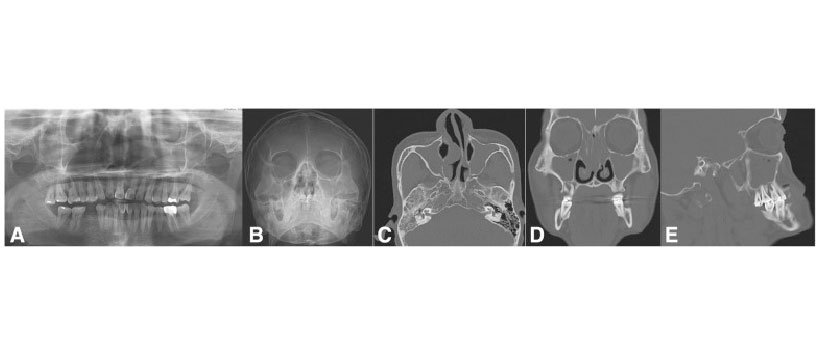

Figura 6: Pansinusitis en ambos senos paranasales que se originan a partir de la infección de la raíz del primer molar derecho. Vista panorámica preoperatoria (a), vista de Water(b), vista axial de la TC que muestra la sinusitis de ambos senos maxilares (c), vista coronal de la TC que muestra una sinusitis completa, incluidos los senos etmoidales y frontales (d), y una vista sagital de la TC que muestra afectación de la lesión patológica radicular del primer molar derecho (e)